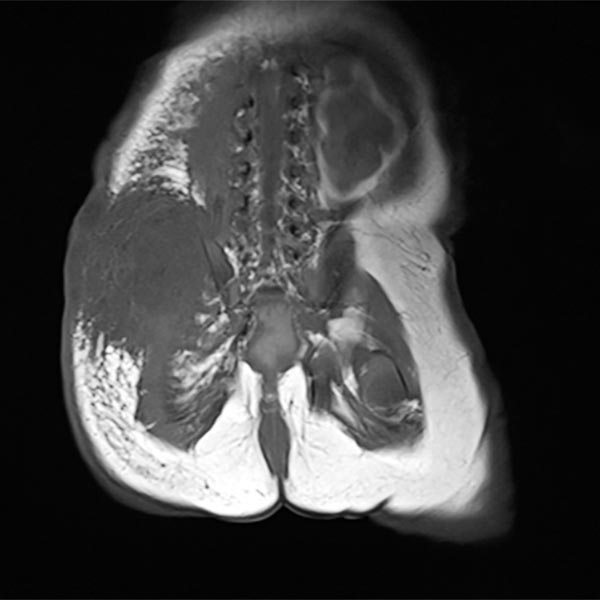

Dynamic contrast-enhanced MR angiography.

Starting in the early arterial phase, the tumor enhances intensively, although not completely.

The venous phase shows intense, homogeneous enhancement without immediate direct venous outflow.

In the late phase, the highly vascularized tumor continues to show strong enhancement without wash-out phenomenon.

In coronal plane T1-weighted, fat-suppressed MRI after contrast administration, the tumor accumulates contrast strongly. The combination of the clinical picture with vascular, reddish-blue tumor immediately after birth, Kasabach-Merritt phenomenon and typical imaging suggests that the diagnosis of kaposiform hemangioendothelioma is very likely.